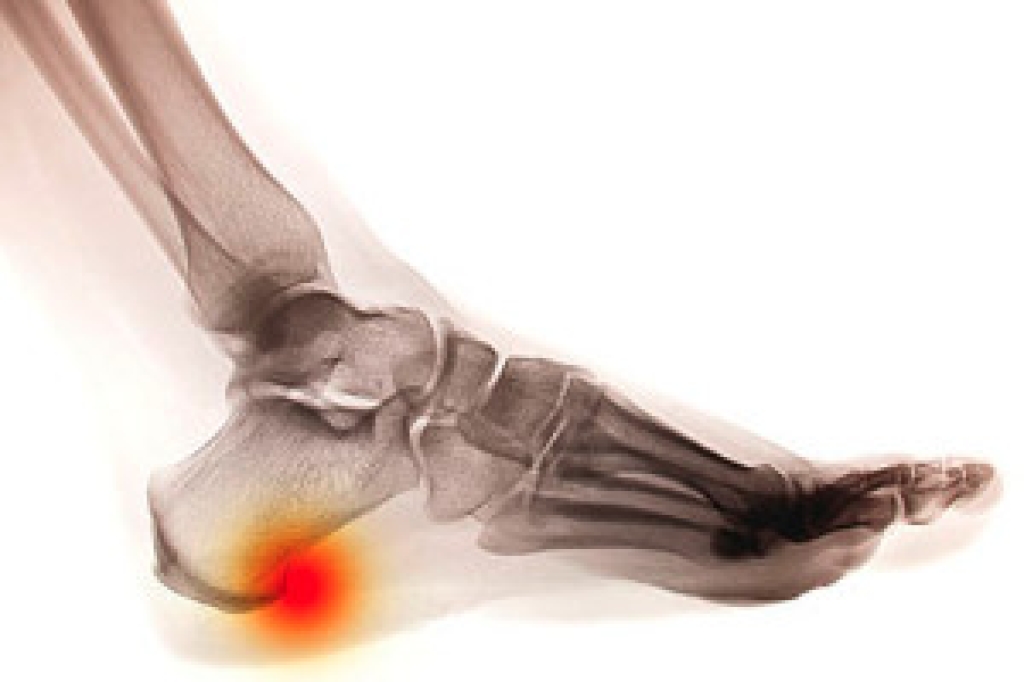

A small and hard protrusion that forms in the heel of the foot is referred to as a heel spur. They can have different shapes that can include being flat, hooked, or pointy. It begins in the heel, and typically grows toward the arch of the foot. It generally produces pain and discomfort while walking, standing, or running. Some patients experience swelling, and the heel may feel achy for the majority of the day. As the aging process occurs, the heel pads may become thinner, and may fail to provide adequate shock absorption. Calcium deposits may gradually develop, the deposits form bony protrusions, which are heel spurs. Patients who are overweight or walk on hard surfaces could be prone to developing this type of foot condition, in addition to wearing shoes that do not fit correctly. Relief may be felt when the foot is elevated, and it is beneficial to wear shoes that have additional cushioning. If you have developed a heel spur, it is advised that you consult with a podiatrist who can properly treat this condition.

Heel spurs are formed by calcium deposits on the back of the foot where the heel is. This can also be caused by small fragments of bone breaking off one section of the foot, attaching onto the back of the foot. Heel spurs can also be bone growth on the back of the foot and may grow in the direction of the arch of the foot.

The pain associated with spurs is often because of weight placed on the feet. When someone is walking, their entire weight is concentrated on the feet. Bone spurs then have the tendency to affect other bones and tissues around the foot. As the pain continues, the feet will become tender and sensitive over time.